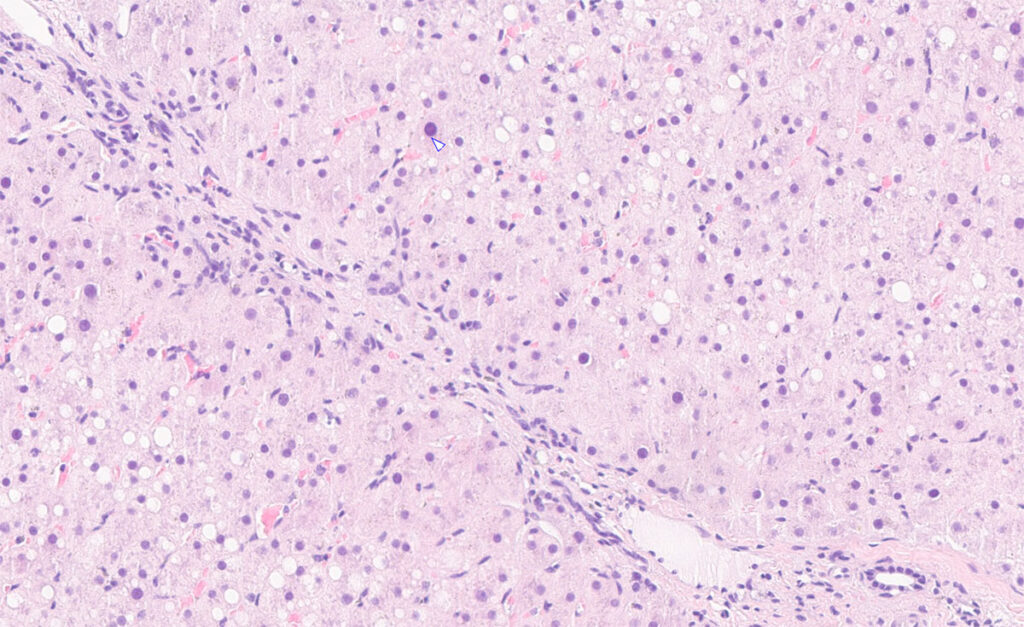

Fig. 1: Liver biopsy of a horse with long-term exposure to mycotoxins and suspected poisonous plants: mild to moderate fibrosis.

Image source: Laboklin

The laboratory diagnostic evaluation of liver diseases in horses is primarily based on the interpretation of liver-specific enzyme activities and functional parameters in serum. Additional laboratory results provide valuable information on the extent of liver damage as well as on possible underlying systemic diseases. Often, further investigations such as sonography and liver biopsy are required to clarify the aetiology (Fig. 1).

Species of Senecio, such as ragwort, can lead to altered liver enzyme activities even in the early stages of intoxication, often without clinical symptoms. The toxic agents are pyrrolizidine alkaloids (PAs), which can cause irreversible liver fibrosis with chronic exposure.